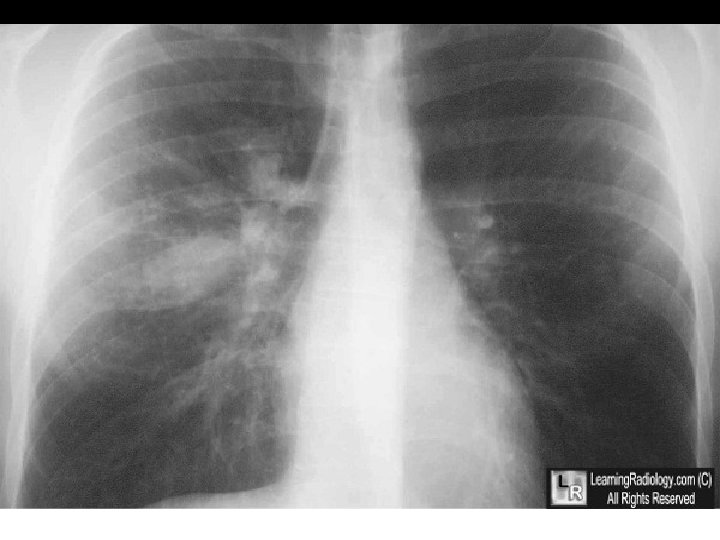

Pneumonia lingula